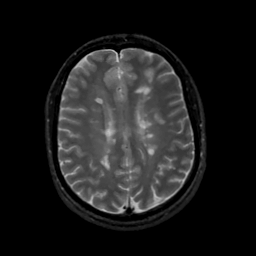

MR Study #13, May 19, 1991 -- Slice #33

[Home][Help][Clinical][Tour 1][Tour 2] Slice 33